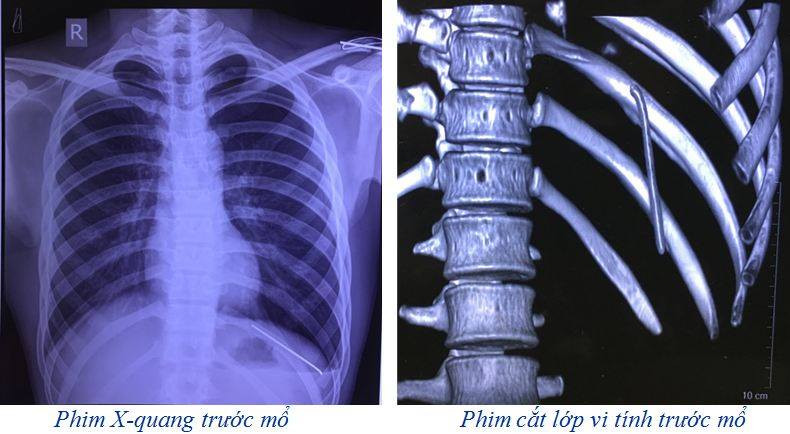

Sau khi thăm khám, các bác sĩ đã chỉ định chụp X-quang và cắt lớp vi tính lồng ngực. Kết quả phim cắt lớp vi tính lồng ngực cho thấy: dị vật dạng kim khí trong KMP trái, tràn khí KMP trái.

Các bác sĩ chỉ định: phẫu thuật nội soi ngực trái để lấy di vật và xử lý tràn khí khoang màng phổi trái. Sau phẫu thuật 1 ngày, người bệnh ổn định, đã được rút bỏ dẫn lưu khoang màng phổi, đi lại và ăn uống gần như bình thường.